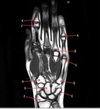

What is letter A?

BASE OF 2ND METACARPAL

74

What is letter B?

TRAPEZOID

75

What is letter C?

CAPITATE

76

What is letter D?

SCAPHOID

77

What is letter E?

RADIUS

78

What is letter F?

ULNA

79

What is letter K?

LUNATE

80

What is letter G?

TRIQUETRIUM

81

What is letter H?

HAMATE

82

What is letter J?

BASE OF 5TH METACARPAL

IP JOINT

84

MCP JOINT

85

HEAD OF METACARPAL

86

What is letter D

87

TRIQUETRUM

88

89

90

HEAD OF 2ND PROXIMAL PHALANX

91

92

BASE OF 2ND MIDDLE PHALANX